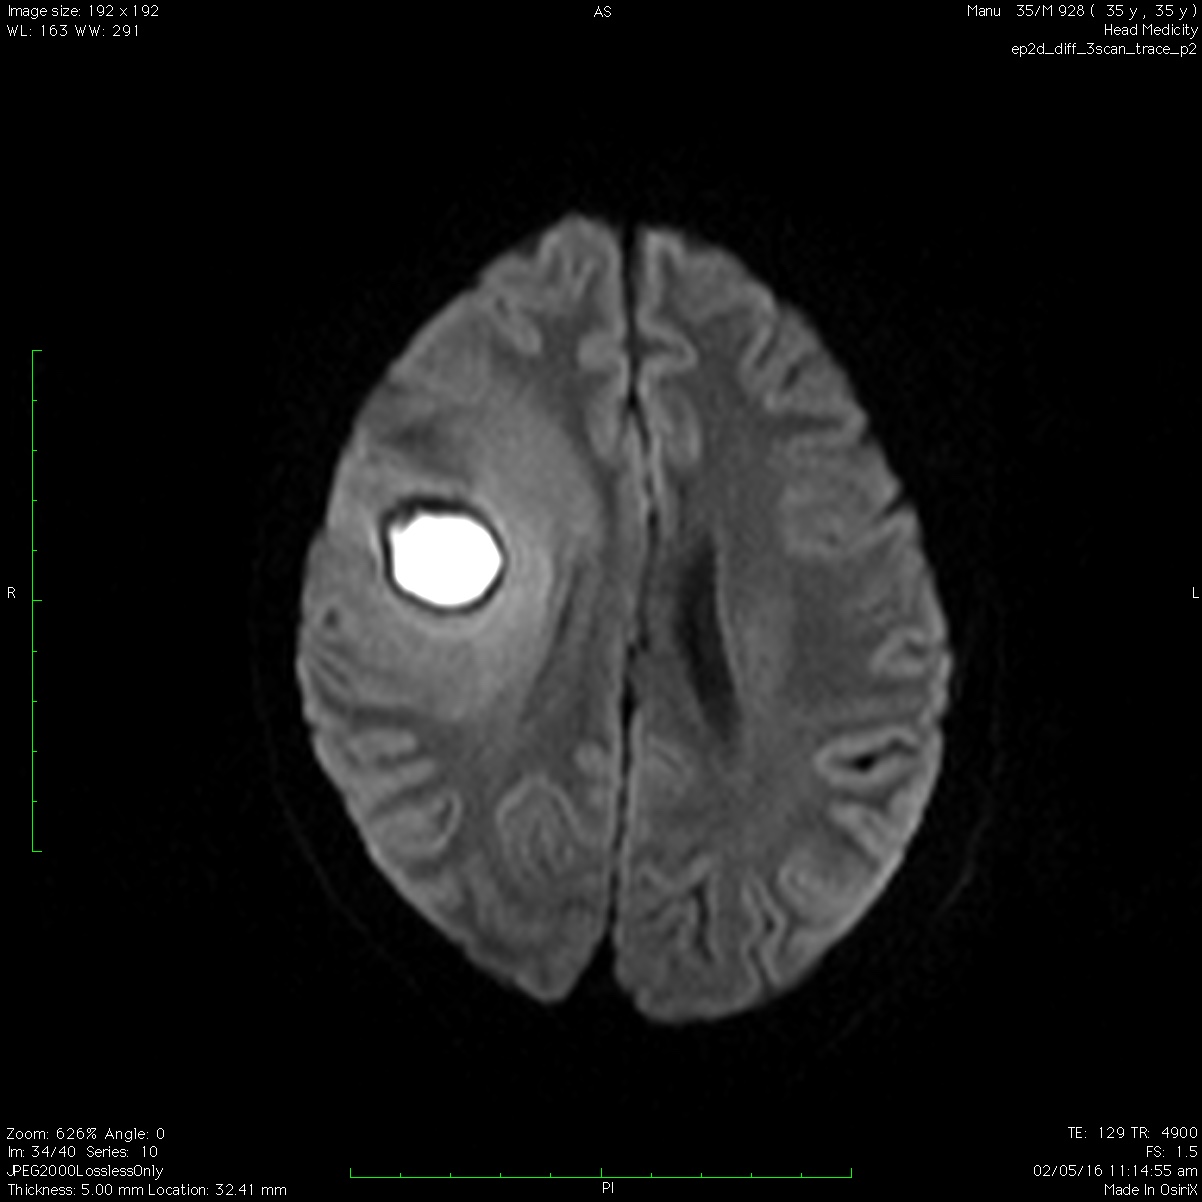

Brain abscess differential diagnosis wikidoc Abscess With White Head a skin abscess will often be round and feel painful and warm. The middle of the lump may feel soft when touched. an abscess is a pocket of pus. When you get an infection, your. cutaneous abscesses may occur anywhere on the skin, but are most common under the arms, at the base of. abscesses are. Abscess With White Head.